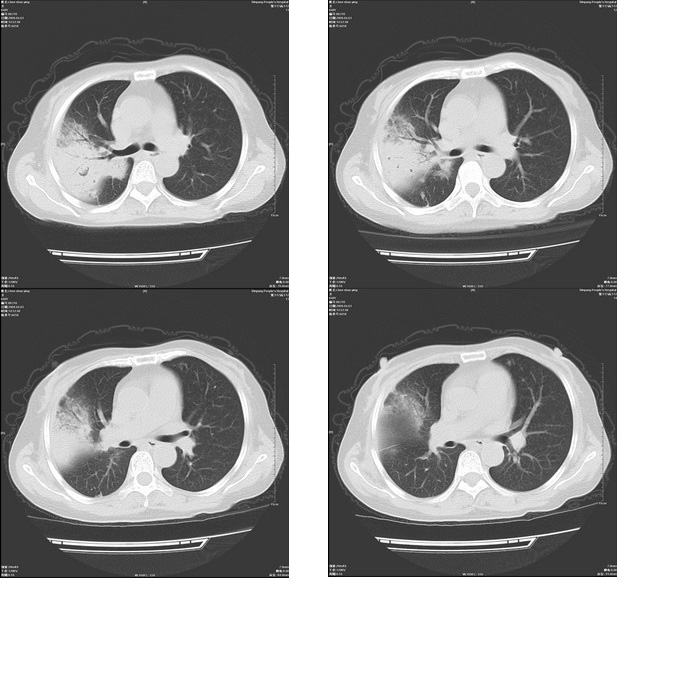

患者,女,48岁,发热伴陈发性咳嗽5天,偶尔痰中带血。体温约38°~40°;白细胞明显减低0.85x10的9次方/升。入院后抗炎、抗痨一周复查病灶明显进展。

右上肺后段实变影,内见支气管气象,肺门未见软组织肿块,气管前方有肿大淋巴结。左下肺见多个类圆形结节影。考虑:1.右上肺后段大叶性肺炎,需进一步检查病原体种类,应多询问病史,条件许可考虑做纤支镜检查2.左下肺结节影性质待定

考虑右上肺后段大叶性肺炎不除外结核,伴双肺结节播散灶,希定期复查。

右肺于酪性肺炎并左肺播散。

考虑两肺继发性肺结核(右肺上叶干酪性肺炎?)。

考虑两肺继发性肺结核(右肺上叶干酪性肺炎)。

右肺干酪性肺炎并左肺播散。

右肺片状实变影,左肺结节影,抗炎及抗捞治疗后病灶进展。

我考虑:不能除外肺炎型肺泡癌可能。建议查痰或活检。